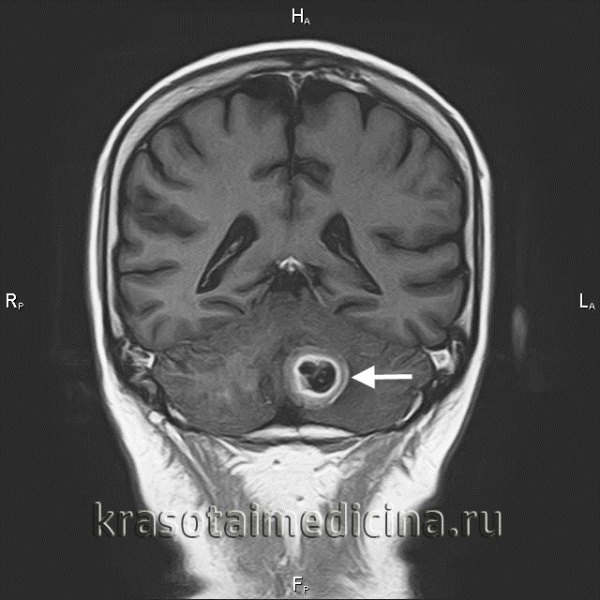

(Слева) При аксиальной МРТ Т1 ВИ у пациента с онемением правой половины лица определяется типичный метастаз в вершине пирамиды, замещающий жировой костный мозг, с распространением в полость Меккеля справа. Обратите внимание на нормальный сигнал в коаном мозге вершины пирамиды слева и ЦСЖ в полости Меккеля.